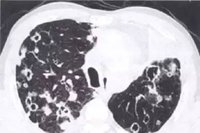

为什么癌症多会转移到肺?这是因为全身静脉血都要通过上下腔静脉回流引到心脏,由右心室通过肺动脉进入肺中进行气体交换。在气体交换过程中,一些由静脉带来的癌细胞通过肺动脉就在肺中安家落户了。肺转移瘤多由血行转移而来。但是也有较少的淋巴转移和直接侵润。淋巴转移多由血行转移到肺小动脉及毛细血管床,然后侵入支气管血管壁周围淋巴结,癌细胞在淋巴结内增殖繁殖,并通过淋巴管在肺内扩散,从而形成了淋巴转移。

一般而言,各种实体恶性肿瘤都可转移到肺。但是临床上最常见的以绒毛膜癌、乳腺癌、恶性软组织肿瘤、肝癌、滑膜肉瘤、胰腺癌、甲状腺癌、肾癌、前裂腺癌、肾胚癌、结直肠癌、食道癌、贲门癌、胃癌、肝癌、胆胆癌等。所以一旦发现肺转移瘤时,就可以按照以上顺序一一排查,找到原发肿瘤。同理发现原发肿瘤时,一定要做肺CT检查,以排除肺癌转移瘤的可能。